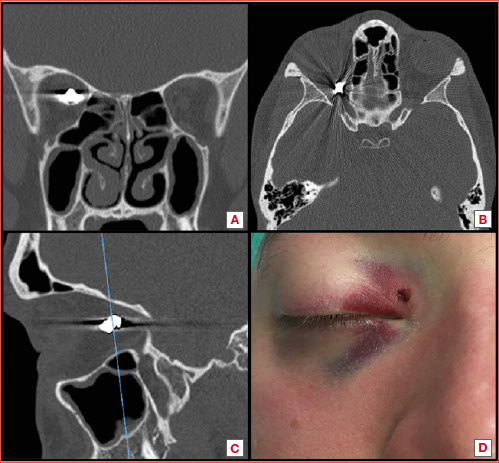

简介眶内异物(IOFB)是一项临床挑战:手术治疗可能会引起争议,并提出了不同的策略。在建议取出异物时,根据异物的位置和性质,人们提出了外部和内窥镜两种方法,但进入眼眶的手术通道和发病率却大不相同:方法:我们对接受内窥镜经鼻手术治疗的 IOFB 病例进行了文献回顾,以评估这种手术在这些病例中的作用。我们还介绍了一例采用内窥镜经鼻方法成功取出眶内子弹的病例,该病例在眼球运动和视力方面取得了良好的效果:结果:采用内窥镜经鼻方法治疗的眶内子弹数量有限。在内侧区,这种方法似乎安全有效。在我们的病例中,患者在术后两个月完全康复,没有明显的长期后遗症:在可行的情况下,经鼻内窥镜方法治疗眶内异物是一种有效的手术技术,可获得最佳疗效和令人满意的恢复。

Methods: We performed a literature review of cases of IOFBs that received exclusive endoscopic transnasal surgical treatment to evaluate the role of this surgery in these occurrences. We also present a case of an intraorbital intraconal bullet that was successfully removed using an endoscopic transnasal approach with good outcomes in terms of ocular motility and visual acuity.

Results: A limited number of cases of IOFBs have been treated with an exclusive endoscopic transnasal approach. When in the medial compartment, this approach appears to be safe and effective. In our case, two months after surgery the patient showed complete recovery with no significant long-term sequelae.